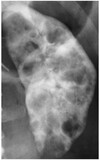

What pathology is seen here?

Polycystic Kidney Disease